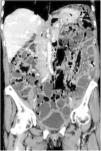

A previously healthy 65-year-old woman presented with symptoms of colicky abdominal pain and intense bloating, nausea and vomiting, and 8kg weight loss within the past 12 months. Her vital signs were stable, and she had no signs of peritoneal irritation. Abdominal angiotomography identified diffuse pneumatosis intestinalis with a predominantly cystic pattern, as well as abundant intraperitoneal free air, free fluid in the pelvic cavity, and no alterations in the mesenteric vasculature (figs. 1-3). Her laboratory test results ruled out gastrointestinal, infectious, oncologic, rheumatologic, pulmonary, and pharmacologic causes that would explain the tomographic findings. The patient received treatment based on metronidazole, probiotics, and prucalopride, and presented with partial symptom improvement, but no remission of the radiologic findings after 6 months of follow-up. The present case illustrates the fact that not all patients with pneumatosis intestinalis or pneumoperitoneum should be managed surgically. Pneumatosis cystoides intestinalis is a rare radiologic finding of unknown etiology. The differential diagnosis includes numerous causes, particularly intestinal ischemia. Treatment consists of antibiotics, prokinetics, hyperbaric oxygen, or endoscopic lesion resection, with varying results. Its clinical progression tends to be chronic and benign.